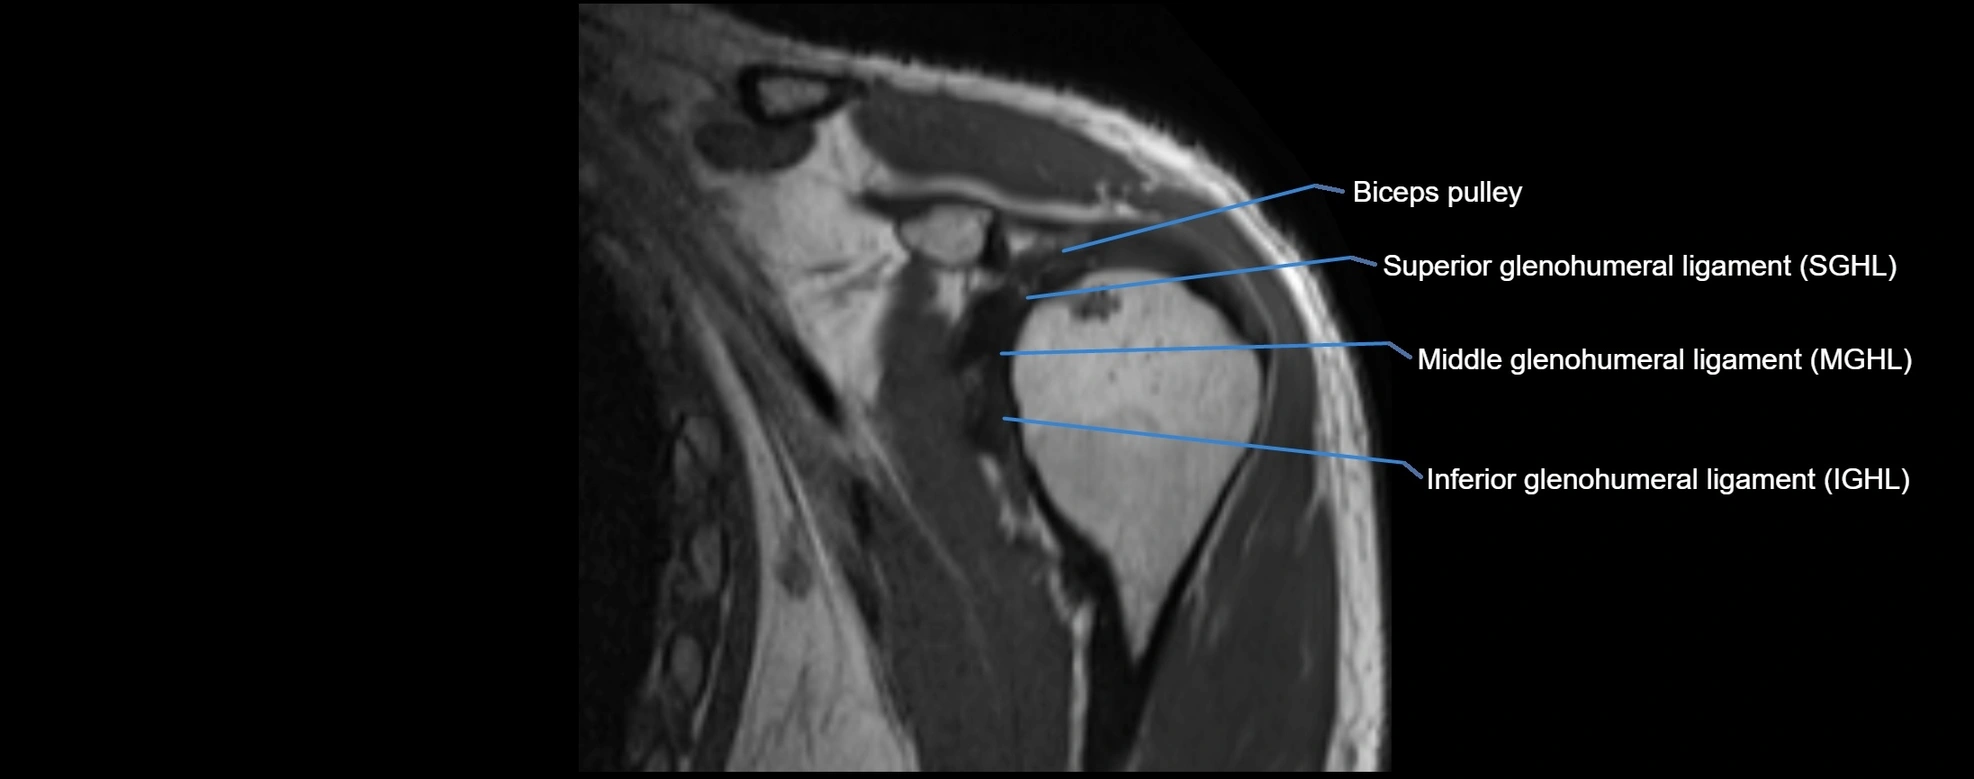

MRI images

image